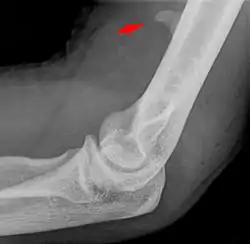

![]() Larger supracondylar process seen on a lateral radiograph of the elbow | |